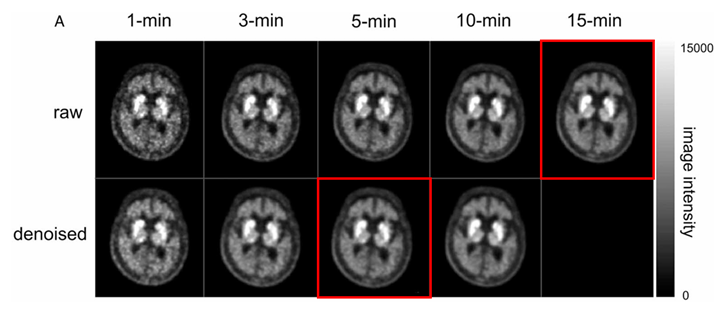

▶ 그림 1. 딥러닝 모델을 통해 복원된 파킨슨 증상 환자들의 PET/CT 영상 비교. 원본(Raw) 영상은 촬영 시간이 짧을수록 노이즈가 심해지지만, 노이즈 제거(Denoised) 영상은 5분 촬영 데이터만으로도 15분 원본 영상과 거의 유사한 고해상도 화질을 보여주며, 진단에 필요한 선조체(Striatum) 섭취 패턴이 명확히 유지되고 있다.

Results: In hospital A, NRMSE, PSNR, and SSIM values improved with scan duration, with the 5-minute DIs achieving optimal quality (NRMSE 0.008, PSNR 42.13, SSIM 0.98). Visual analysis rated DIs from scans ≥3 minutes as adequate or higher. The mean BP ND differences (95% CI) for each DIs were 0.19 (-0.01, 0.40), 0.11 (-0.02, 0.24), 0.08 (-0.03, 0.18), and 0.01 (-0.06, 0.07), with the CIs significantly decreasing. ISRs with the highest effect sizes for differentiating NPD, IPD, and APD (PP/AP, PP/VS, PC/VP) remained stable post-denoising. External validation showed 10-minute DIs (hospital B) and 1-minute DIs (hospital C) reached benchmarks of hospital A's image quality metrics, with similar trends in visual analysis and BP ND CIs. Furthermore, motion artifact correction in 9 patients yielded DSC improvements from 0.89 to 0.95 in striatal regions.